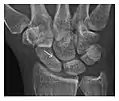

High-energy trauma fractures

Occult osseous injuries may result from a direct blow to the bone by compressive forces of adjacent bones against one another or by traction forces during an avulsion injury. Lesions in the tibial plateau, hip, ankle, and wrist are often missed. In a tibial plateau fracture, any disruption of the posterior and anterior cortical rims of the plateau should be sought. Impaction of subchondral bone will appear as an increased sclerosis of the subchondral bone (Figure 1). In the hip, posterior acetabular fractures also present subtle radiographic findings. The acetabular lines should then be carefully examined keeping in mind that the posterior rim, which is harder to see on X-rays, is more frequently fractured than the anterior rim (Figure 2). In the wrist, detection of carpal bone fractures is often challenging, with up to 18% of scaphoid fractures radiographically occult. Carpal fractures, especially the scaphoid, are associated with the risk of avascular necrosis. In apparently normal wrist radiographs from symptomatic patients, if there is history of a fall on an outstretched hand with pain in the anatomic snuffbox, suggesting scaphoid injury, the initial examination with posteroanterior, lateral, and pronation oblique views must be complemented by other specific views such as supination oblique and the "scaphoid" view A careful examination of cortices for evidence of discontinuity or offset and cancellous bone for lucency is necessary (Figure 3).[1]

Figure 3: A 26-year-old man presenting with wrist pain after being assaulted. (a) Initial anteroposterior radiograph shows a subtle linear lucency within the scaphoid extending to the scaphocapitate articular surface that was overlooked (arrow). (b) Initial "scaphoid" view was negative. (c) Followup anteroposterior radiographs, 12 days later, shows obvious scaphoid fracture (arrows).[1]